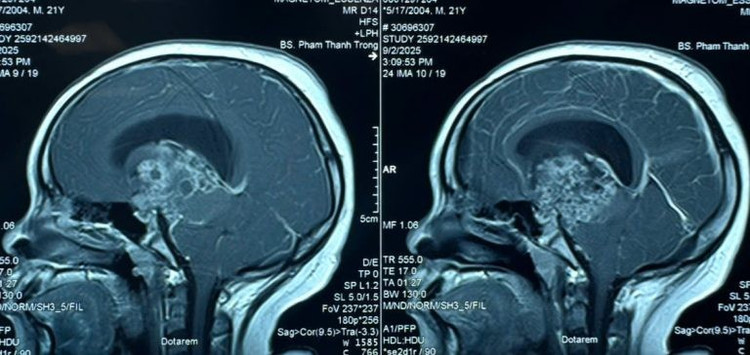

Kết quả cho thấy, anh S. có khối u não lớn kích thước 6cm, khối u nằm ở vị trí giữa não gây chèn ép dẫn đến hiện tượng giãn não thất, làm dịch não tủy không thể lưu thông – nguyên nhân khiến người bệnh rơi vào hôn mê.

Hình ảnh MRI khối u sọ hầu - Ảnh BVCC

Theo khai thác bệnh sử, được biết bệnh nhân S. đã từng phẫu thuật lấy khối u sọ hầu cách đây 8 năm. Thời điểm đó, bệnh nhân có chỉ định xạ trị bổ túc sau mổ để điều trị tiếp khối u nhưng vì hoàn cảnh gia đình khó khăn nên bà P. đã ngừng việc điều trị tiếp cho con. Đây có thể là lý do khiến khối u tái phát sớm, khối u ngày càng lớn gây chèn ép não bộ.